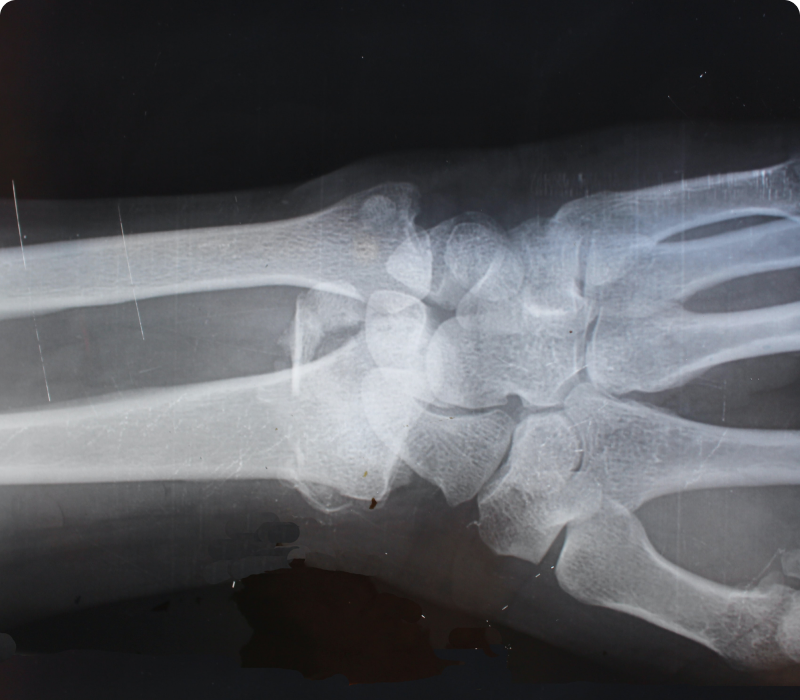

4. Medical imaging

If needed; you will be referred to the local radiology centre for necessary views to be taken, to visualise the location of any spinal or extremity concerns, reveal any abnormalities, and help us make your care more specific to your condition.